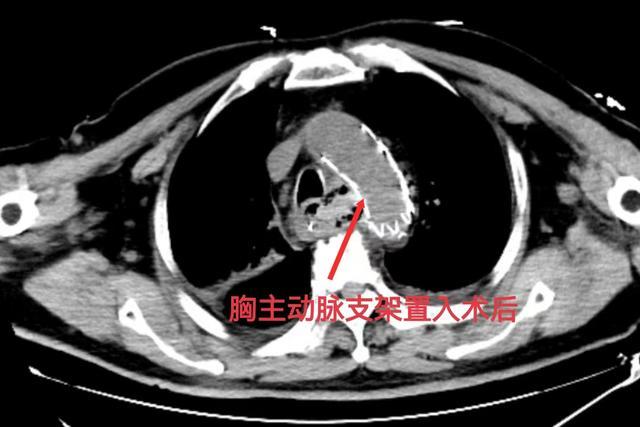

同时,由介入团队开通急救绿色通道,为患者施行胸主动脉造影+覆膜支架植入术进行止血,并做好大血管外科随时开胸手术的准备;后续由消化科进行床旁胃镜检查及空肠管置入术,胸外科和普外科做好开胸准备。

幸运的是,介入手术止血十分顺利;消化科通过胃镜检查发现:食管黏膜破损、食管内有较多血凝块,但无活动性出血,也未见明显异物,随后置入空肠管,给予肠内营养。